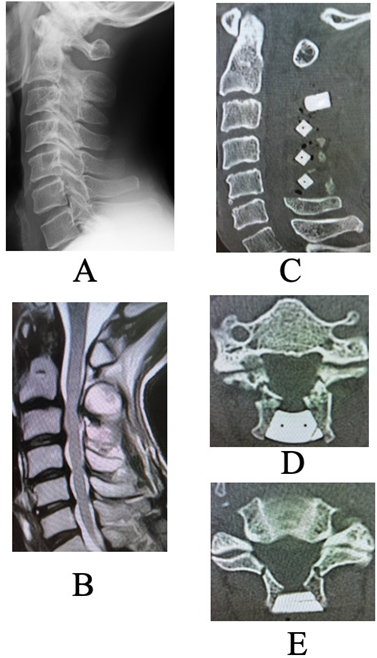

Figure 1: (a and b) Pre-operative images before the initial surgery. (a) Plain lateral radiographs Neutral position. No abnormal alignment or dynamic instability was observed. (b) Sagittal magnetic resonance imaging image. Spinal cord compression is evident at the C2/3, C4/5, and C5/6 levels. (c, d, e): Post-operative computed tomography after the initial surgery. (c) Sagittal view (d) Axial view at the C2 lamina level (e) Axial view at the C3 lamina level. Lamina inner plate damage at the lateral gutters is observed at both C2 and C3, but the spacers are well positioned, and sufficient laminar opening was achieved. At the C3 level, the lateral gutters were created medial to the medial pedicular line.

A C2–C5 double-door laminoplasty was performed. Post-operative computed tomography (CT) revealed a narrow lateral gutter at C3 and damage to the inner lamina, but adequate opening of the lamina was achieved, and the spacer was positioned appropriately (Fig. 1). In the current pre-operative plain radiographs, there was no deterioration in alignment, and no evidence of vertebral slippage or intervertebral instability (Fig. 2).